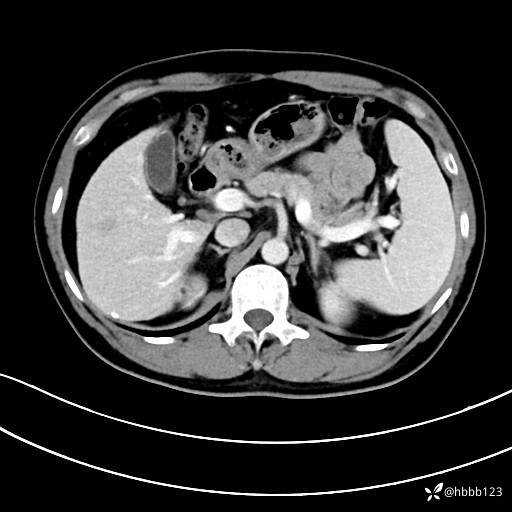

门诊完善上腹部CT平扫+增强。

静脉期: